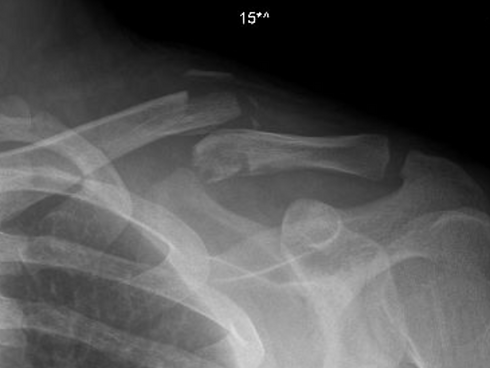

What is it? This page provides general information as well as my personal notes and treatment algorithms for commonly seen conditions in my shoulder, elbow, and upper extremity reconstruction practice. There are conditions that I see and treat that are not listed - please contact my office for more specific information. (more diagnoses coming soon!)